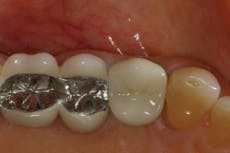

Approximately 12 weeks after healing, the area was inspected (Figure 5) and a new radiograph was taken to visualize the underlying bone. There was adequate width and height to place an implant that would replicate the premolar.

Fig. 5 — Healed ridge (5894)